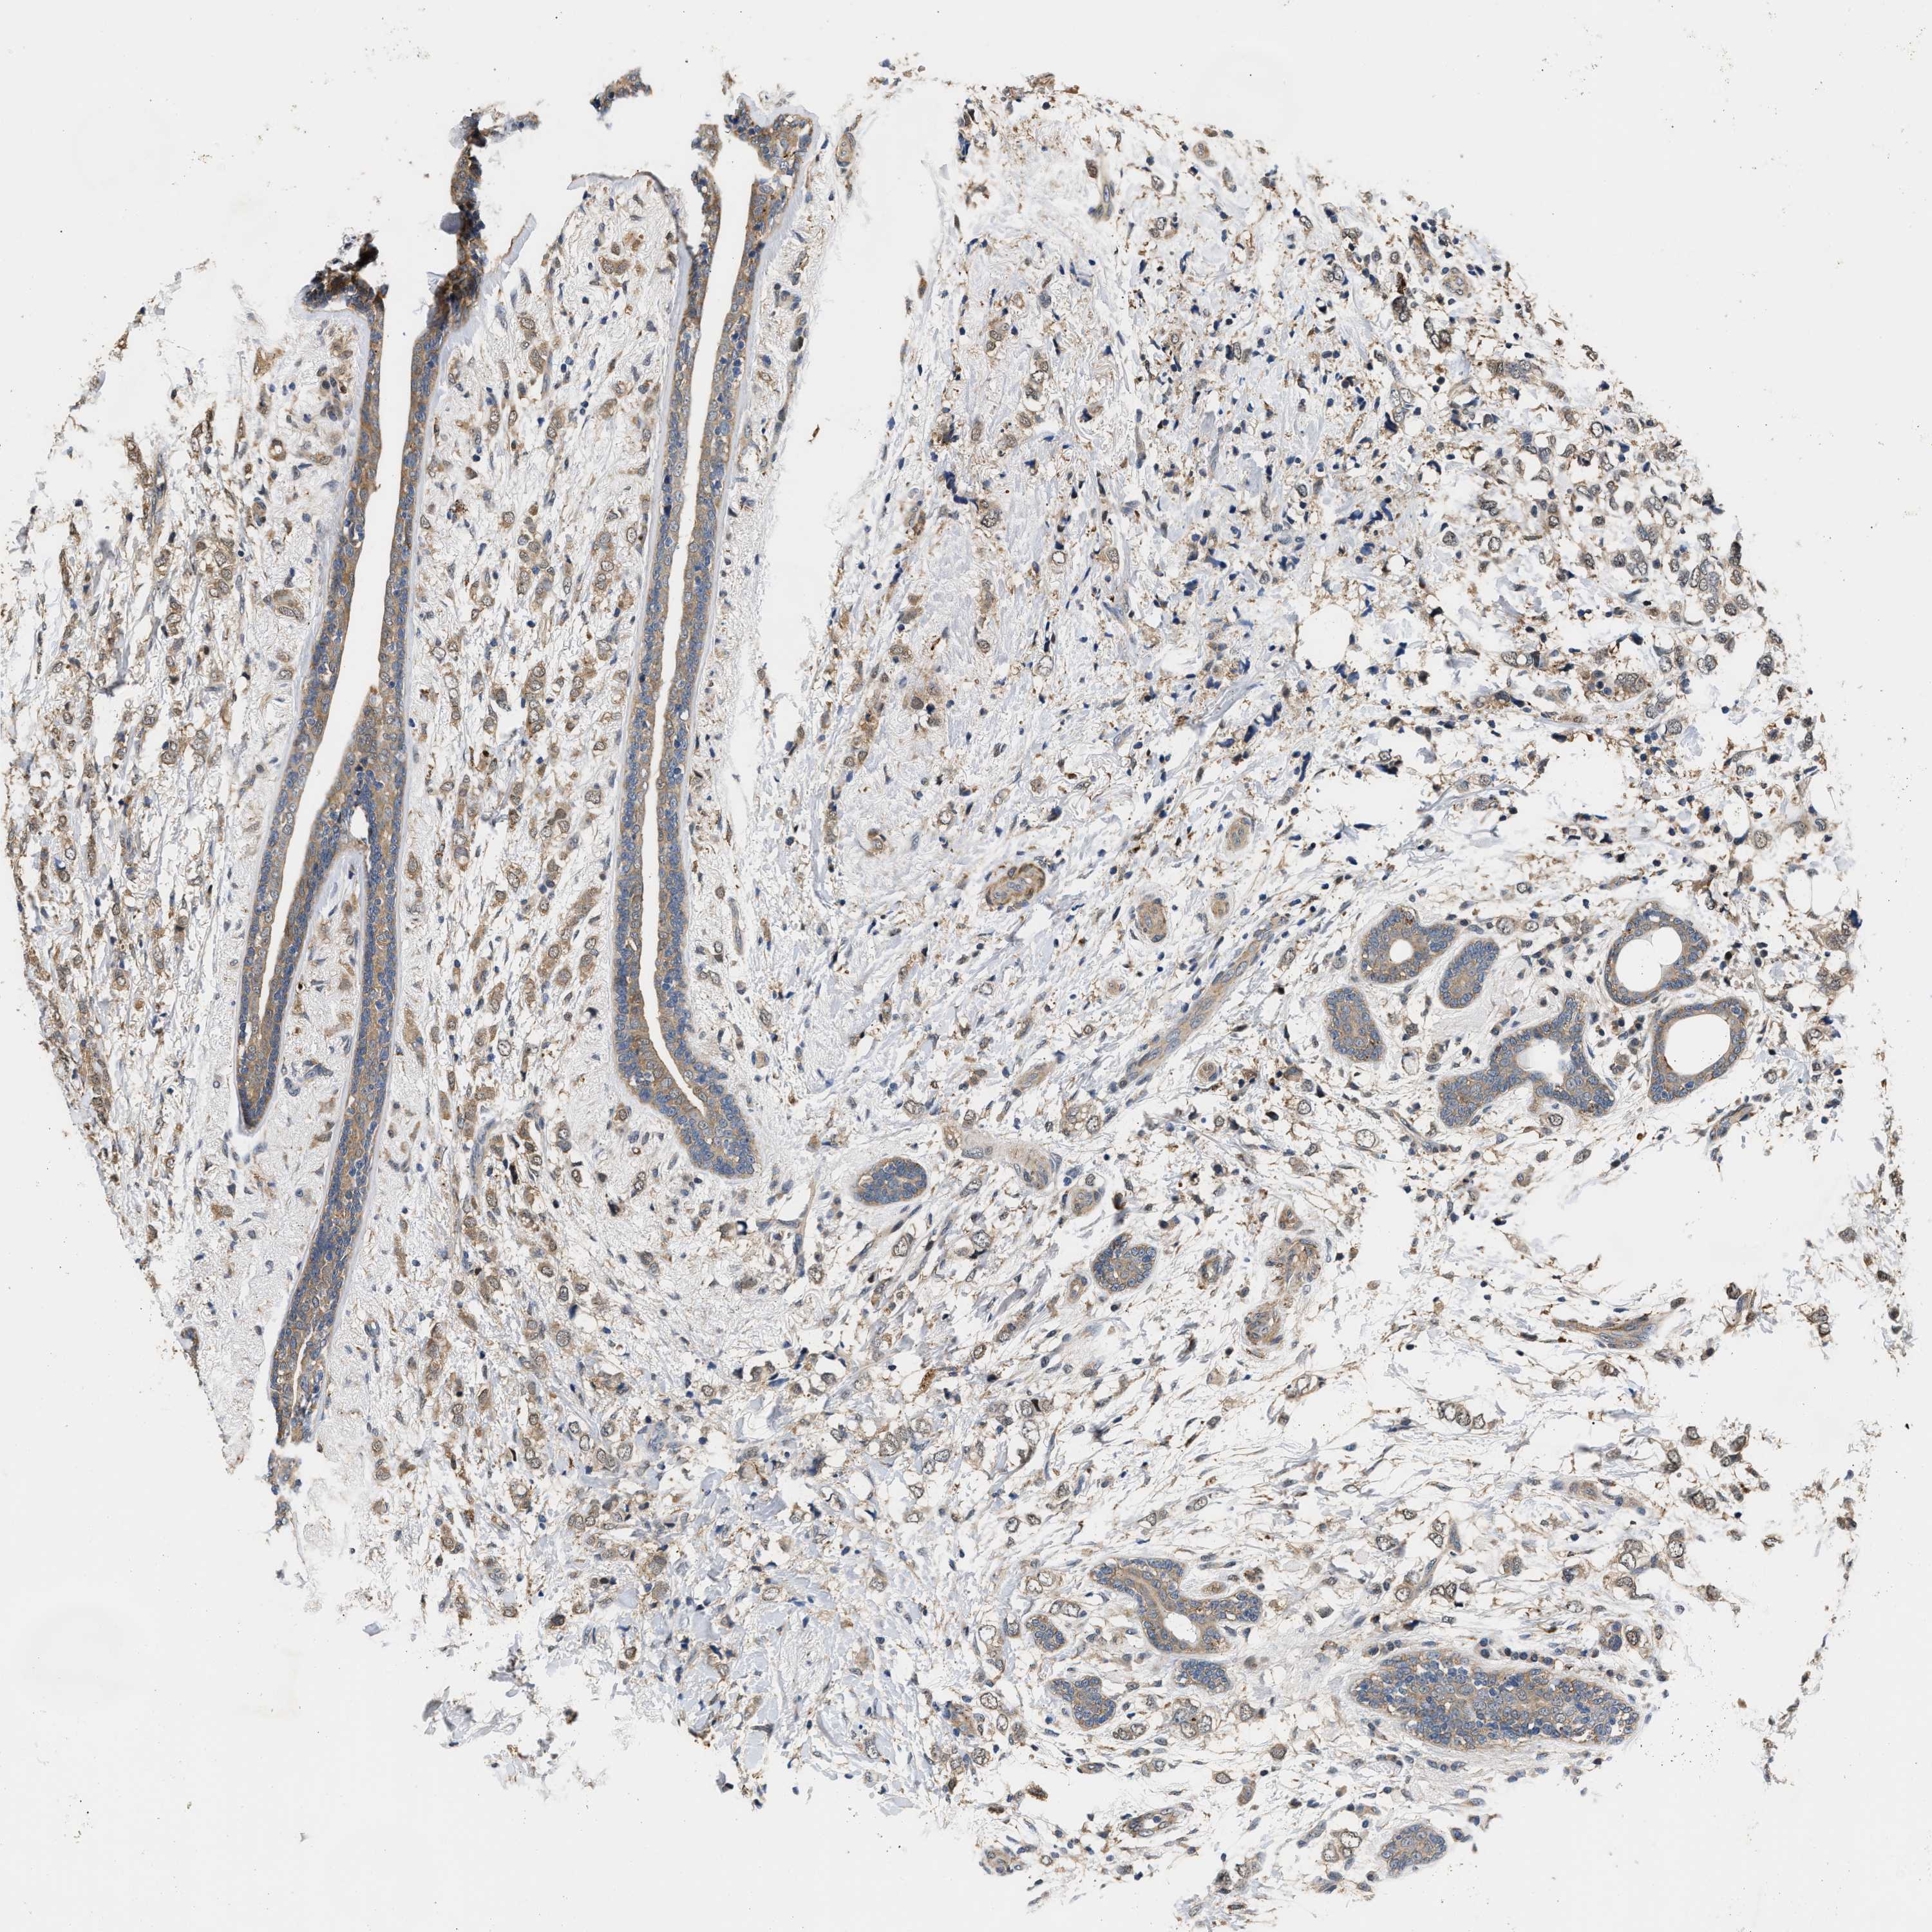

BRCA TCGA BRCA VALIDATION PROTEIN EXPRESSION